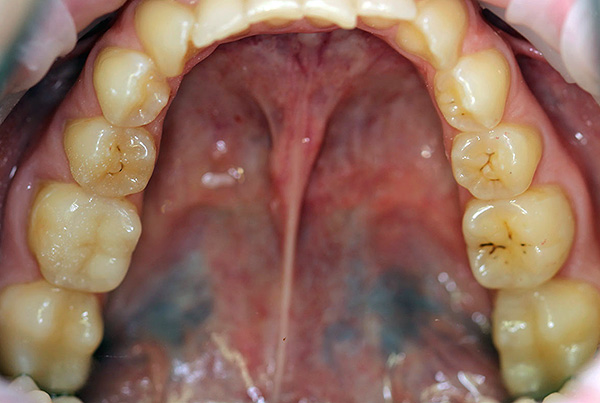

Em casa, esses defeitos nem sempre podem ser identificados corretamente - eles podem parecer manchas acinzentadas ou marrons, pontos, ranhuras. Se esse defeito estiver no espaço interdental, pode ser difícil perceber. Defeitos nos molares pequenos e grandes inferiores são claramente visíveis (um exemplo é dado na fotografia abaixo).